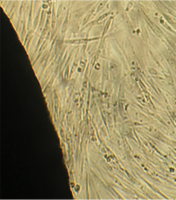

Вид монослоя и структура клеток не отличались от обычных в течение всех четырех суток наблюдения (рис. 32).

Это свидетельствует об умеренной стимуляции пролиферации фибробластов в культуре под влиянием недеминерализованной спонгиозы (таб. 9.).

2 серия экспериментов. В культуральные чашки помещали образец исследуемого материала (кусочек недеминерализованной спонгиозы серии «Лиопласт»® объемом 125 куб. см), после чего высевали фибробласты в концентрации 20000 клеток/см².

Наблюдение через сутки показало, что фибробласты хорошо пристают к дну культуральной чашки, образуют равномерный монослой с плотностью 311 клеток/мм².

Фибробласты были распластаны по дну чашки, имели обычную для этих клеток удлиненную форму, 2-4 отростка, клеточная и ядерная оболочки четко контурировали.

Цитоплазма представлялась гомогенной (рис. 33). Большинство клеток имели одно центрально расположенное ядро правильной округлой формы с 1 или 2 ядрышками.